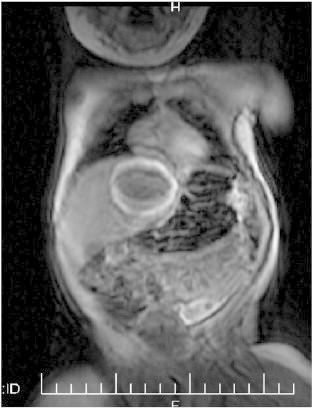

Upon the diagnosis of the mother, the infant was brought back to the hospital and was found to have a β-hCG level of 339,000 mIU/ml. CT scan showed a 4.5 × 3.5 cm liver mass (Fig. 2), eight lung lesions (the largest measuring 3 cm), as well as bilateral ocular lesions. Physical exam revealed his liver palpable 3 cm below the costal margin. Based on these findings, the diagnosis in the mother and elevated β-hCG levels, the diagnosis of disseminated infantile choriocarcinoma was made. It was determined that the risks of tissue biopsy including excessive bleeding outweighed the potential benefits.

Fig. 2.

CT scan of the baby showing a 4.5 × 3.5 cm liver mass.